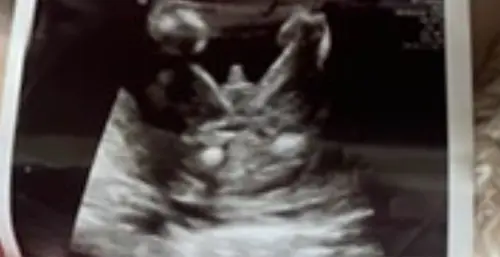

Ik heb een vroege geslachtsecho gedaan 13 weken, vorige zoon ook gedaan.

Je ziet overduidelijk een penis maar toch anders bij mijn eerste zoon, is dit van een andere hoek of iets?